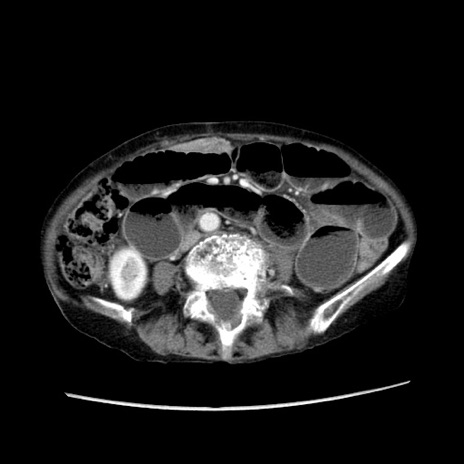

症例25(横断像)

【症例】80歳代女性

【主訴】胸のつかえ感

【現病歴】約9時間前に食後から胸のつかえた感じあり、嘔吐あり、来院。

【既往歴】胃癌(全摘)、胆摘、虫垂炎

【身体所見】心窩部に圧痛あり、反跳痛なし。

【データ】WBC 5700、CRP 0.05